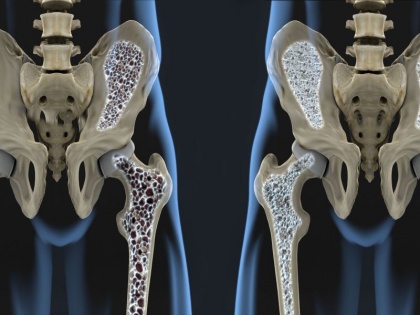

ऑस्टियोपोरोसिस हड्डी का चयापचय रोग है, जो हड्डियों के घनत्व में कमी से होता है। आसान भाषा में कहें, तो एक ऐसी समस्या है, जिसमें कैल्शियम की कमी के कारण हमारी हड्डियां कमजोर होने लगती हैं। इस रोग में हड्डियों के फ्रैक्चर का अधिक खतरा होता है।

डब्ल्यूएचओ की हालिया रिपोर्ट के अनुसार हार्ट डिजीज के बाद ऑस्टियोपोरोसिस विश्व की दूसरी सबसे ज्यादा प्रभावित करने वाली बीमारी है। दुर्भाग्यवश इस रोग के शुरूआती संकेत और लक्षण दिखाई नहीं देते हैं और मरीज की 'बोन मास' व 'बोन टिश्यू' (जो हड्डियों की ताकत होती है) का निरंतर ह्रास होता है।

इस वजह से धीरे-धीरे हड्डियां कमजोर और खोखली होती चली जाती हैं। आजकल यह समस्या बहुत आम हो गई है। कम उम्र के युवा भी इसके चपेट में आ रहे हैं और इसकी सबसे बड़ी वजह खराब खानपान और खराब जीवनशैली है।

एक्सपर्ट के अनुसार, शारीरिक गतिविधियों में हिस्सा नहीं लेने वाले लोगों को इसका सबसे ज्यादा खतरा होता है। इसके अलावा जेनेटिक फैक्टर, प्रोटीन, विटामिन डी और कैल्शियम की भी शरीर में कमी इस रोग से व्यक्ति को जकड़ लेती है। ज्यादा ड्रिंक्स के सेवन के साथ स्मोकिंग, डायबीटीज, थायरॉइड जैसी बीमारियों के साथ महिलाओं में जल्दी पीरियड्स खत्म होना या मेनोपॉज की स्थिति में यह समस्या हो सकती है।